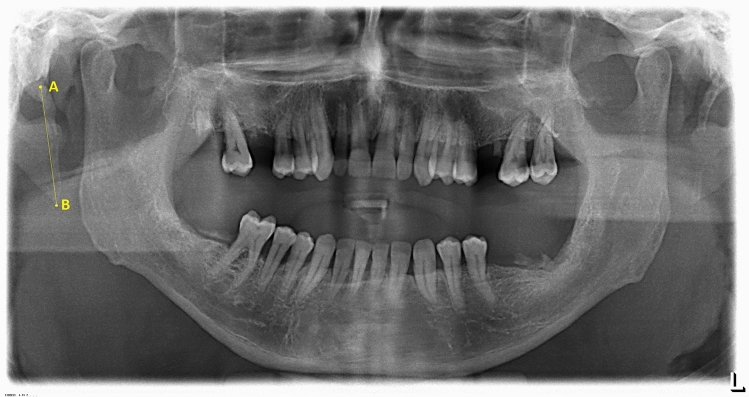

When an elongated stylohyoid process (ESP) was observed, its length was measured, according to the study of Jung et al. [5]. According to his study, the measurements are performed from the frontal view of the styloid process, where it leaves the tympanic plate of the temporal bone. The panoramic radiograph in this area presents a thin transparent line between the styloid process and the tympanic bone, which corresponds to the bone cleft present. The starting point of measurement (A) is situated where this radiolucency fades and the styloid process starts. On the other hand, the ending point of the measurement (B), is the radiopaque tip of the styloid process. The length of the line going from A to B is considered the length of the elongated styloid process.

The lengths of these mineralized areas were measured using the electronic ruler and recorded.

Values higher than 25 mm were adopted as the manifestation of an elongated stylohyoid process. The position of the ESP was recorded as well: bilateral or unilateral (right side or left side). In the end, ESPs where broken into two categories: segmented and non-segmented. If no distinction between the stylohyoid ligament complex and the ossified stylohyoid ligament was possible, the entire osseous length of the stylohyoid apparatus was measured as a single unit and was considered non-segmented. Otherwise, if the ESP appeared fragmented, the segments were individually measured and then added together, obtaining the total osseous length.

Fig. 2.

ESP measurement